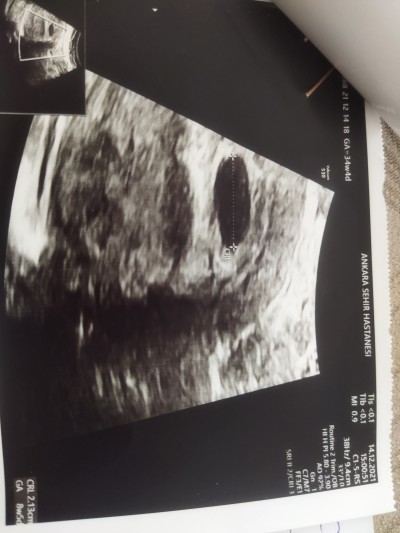

Alttan bakildiginda kalbi zayif atiyor tekrar bidaha gel demislerdi ozaman 7+2 haftaliktim hem kasiktan hem alttan usg resimleri bunlar persembe tekrar gidicem bakalim doktor ne diyecek resimler olumlumu bakarmsnz arkadaslar

Gebelik haftası 8+2

Alttan baktirmasaydim bos gebelik dedi kurtaj yapacakti bende kabul etmedim alttan bakti bebegi gordu kalbi zayif atiyor dedi

Eveet , minigimiz görünüyor orada , işaretlenmiş

Kalbi zayif atiyor dedi bide ozaman 7 +2 di 6+2 dedi snra 8+5 dedi kagittada yaziyor anlamadm vallahi